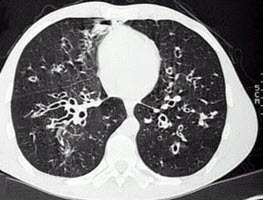

男,38岁,咳嗽、咳痰、咯血,结核菌素实验(-),结合CT图像。最可能的诊断是()

A.支气管扩张

B.肺囊虫病

C.肺囊肿

D.间质性肺炎

E.特发性肺间质纤维化